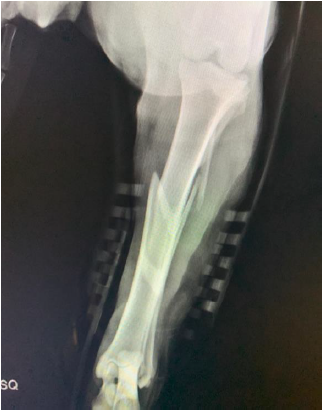

Uma fêmea canina de três anos de idade e com 27 kg foi atropelada ao fugir de pátio onde vivia. Ao retornar para casa, o tutor detectou que o animal não apoiava mais o membro pélvico esquerdo, sendo a paciente levada para consulta veterinária. No exame clínico, não foram detectadas soluções de continuidade na pele, sendo observada dor, crepitação e falta de alinhamento anatômico do referido membro. Após realização da atadura de Robert Jones, foi realizado o exame radiográfico do local afetado em duas incidências perpendiculares entre si e obtidas as imagens abaixo. Considerando a necessidade de encaminhamento para tratamento cirúrgico, assinale a alternativa que contém a classificação e o tratamento cirúrgico indicado para o caso em questão: